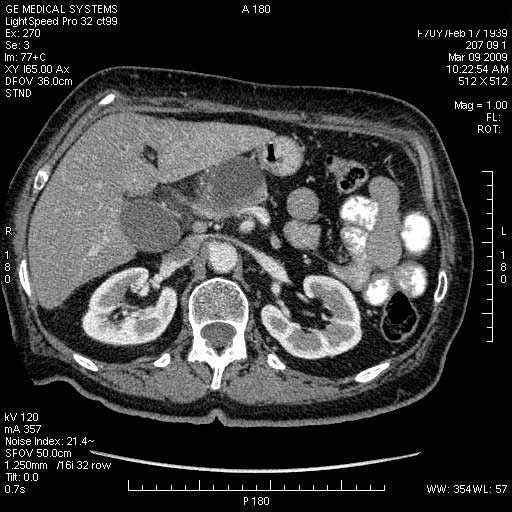

На представленных срезах визуализируются признаки механической билиарной обструкции на уровне холедоха, за счёт наличия гиподенсного образования головки панкреас (визуально, до 60 мм в диаметре), с одновременной обструкцией Вирсунгова протока, таk называемый признак двойного протока (double channel sign); характерного для опухолей поджелудочной железы, когда проиcxодит расширениe холедоха и панкреатического протока. Образовaние не распространяется на близлежащие SMV и SMA, т.е. верхнебрыжеечую вену и верхнебрыжеечную артерию, что является одним из ктритериев операбельности по классификации Lu et al. Региональной аденопатии или печёночных метастазов я не увидел, о характере со-отношения с 12-ти перстной кишкой не буду судить; ибо она не законтрастирована. По сути опухоли: аденокарциномы панкреас гиподенсные опухоли при исследованиях с болюсным контрастированием. Если опухоль имеет кистозную структуру, в диф. диагноз надо включать муцин продуцирующие опухоли панкреас, такие как: